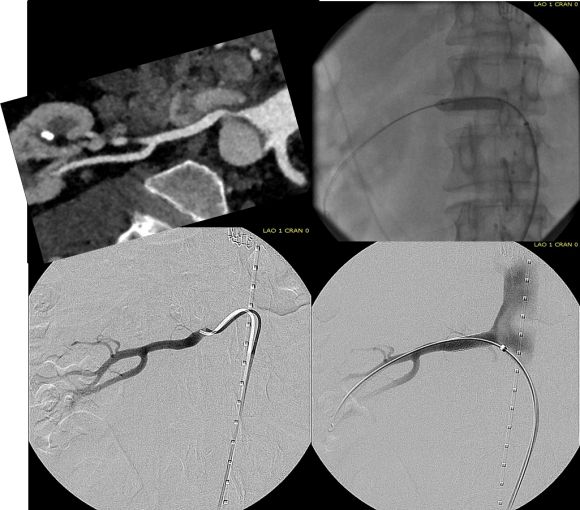

The common femoral endarterectomy is done from its distal most point and the Vollmer ring is used to mobilize the plaque. A Moll Ring Cutter (LeMaitre Vascular) is then used to cut the plaque.

The plaque is extracted and re-establishes patency of the EIA.

The plaque end point is typically treated with a stent -in this case, the common iliac plaque was also treated.